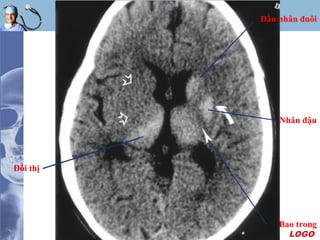

Nhân đậu

Bao trong

Đầu nhân đuôi

Đồi thị